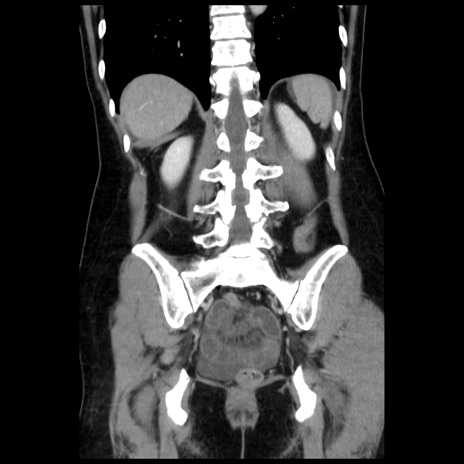

症例10(冠状断像)

【症例】 50歳代女性

【主訴】 腹痛

【現病歴】前日生レバーを食べた。今朝に排便あり。 昼前に突然発症の腹痛を生じ、当院救急外来を受診した。

【既往歴】 子宮筋腫にてで子宮全摘後

【身体所見】 意識清明、腹部:平坦、軟、下腹部やや左を中心に圧痛・反跳痛あり、筋性防御あり

【データ】WBC 7800、CRP 0.07